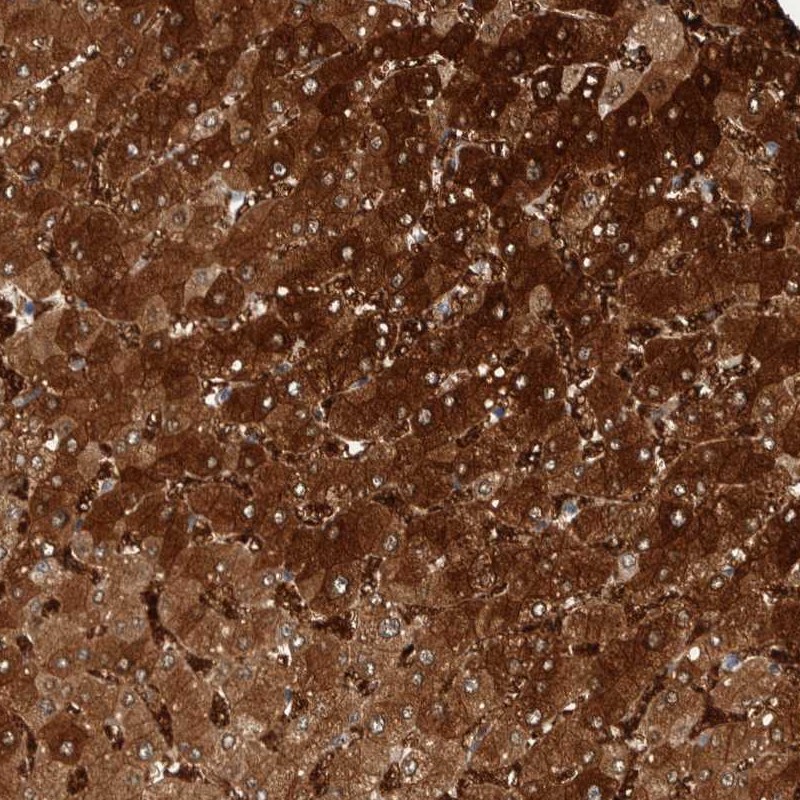

Immunohistochemical staining of human liver shows strong cytoplasmic positivity in hepatocytes.